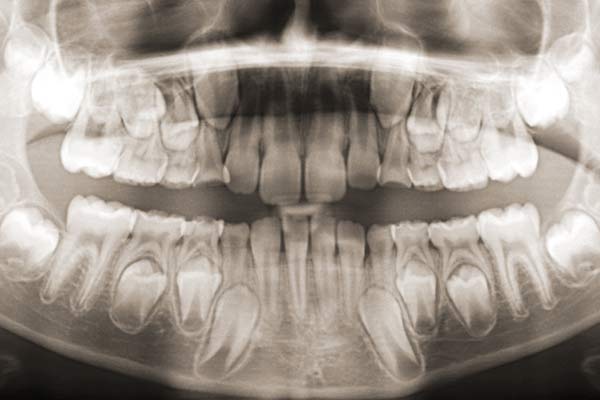

Digitales Röntgen - Panoramaschichtaufnahme (OPT)

Diese Art des Röntgenbildes ist eine Übersichtsaufnahme aller Zähne, Kiefer und Kiefergelenke. Sie dient als Grundlage zur Erkennung und Beurteilung von Nichtanlagen bzw. überzähligen Zahnanlagen, verlagerten Zähnen, Weisheitszähnen und krankhaften Veränderungen des Knochens, der Kiefergelenke, der Zahnwurzeln und der Kieferhöhle. Die daraus abgeleiteten diagnostischen Erkenntnisse stellen mitunter die Weichen für das weitere therapeutische Vorgehen des Kieferorthopäden.